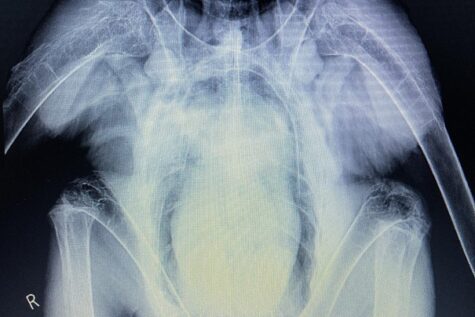

また、岩手県鳥獣保護センターからの診療依頼があり、衰弱して保護された野生のオジロワシの治療を行いました。オジロワシは絶滅が心配されている大型の猛禽類で、岩手県内で保護されることは非常にまれです。呼吸器症状が見られことから、真菌性の肺炎や鉛中毒など様々な原因を疑い検査や治療を試みましたが、残念ながら命を救うことは出来ませんでした。岩手の豊かな自然や野生動物たちを守ることも動物園のとても大切な役割です。多くの命を救えるように体制を整えていきたいと思います。